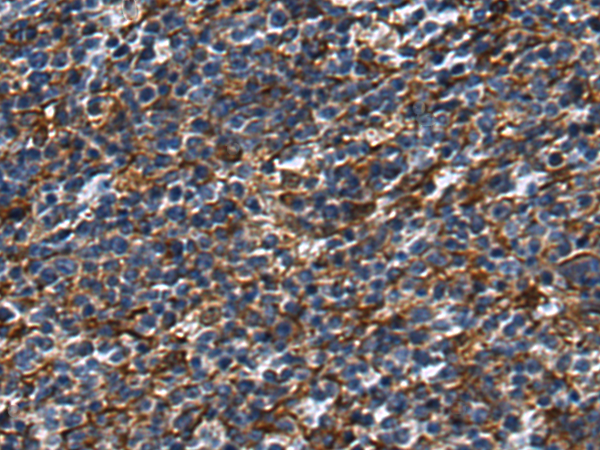

IHC positive control: |

Human thyroid cancer and Human tonsil |

200-400 |